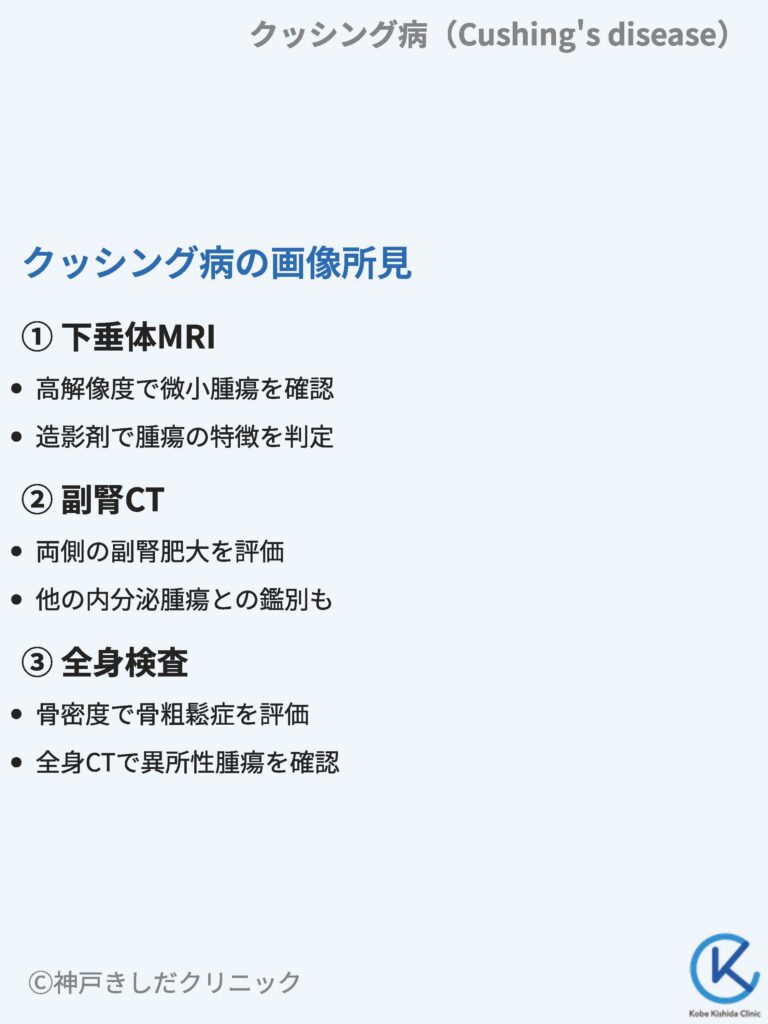

難治性甲状腺がんに対する標的アルファ線核医学治療 (Targeted, クッシング病(Cushing's disease) – 内分泌疾患 - 神戸きしだ,

クッシング病(Cushing's disease) – 内分泌疾患 - 神戸きしだ, 腎盂・尿管・膀胱癌 第2版(腫瘍病理鑑別診断アトラス) 宮居 弘輔,